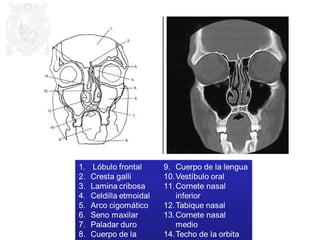

1. Cresta frontal

2. H. frontal

3. Sustancia blanca

4. Cisura o surco

5. Hemisferio parietal

6. Haz cerebral del cerebro